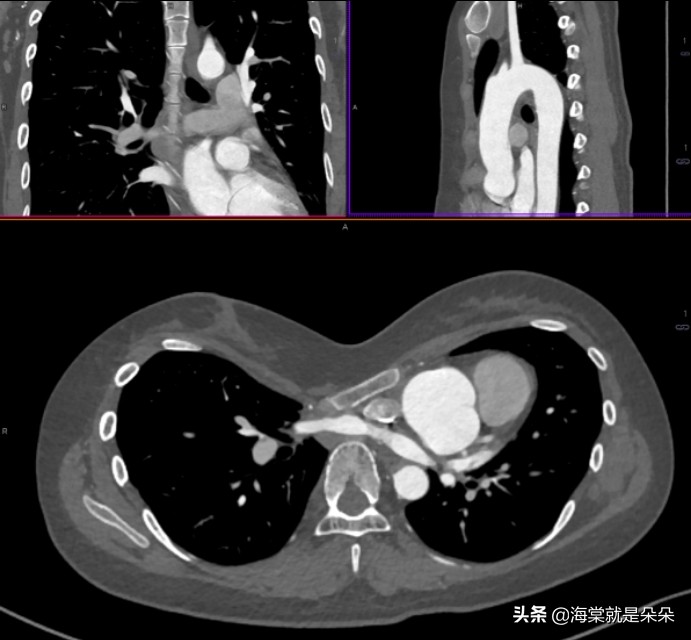

这个女孩20岁才来就诊,Haller指数达到了16!胸骨体都快贴到胸椎了!心脏大血管受压迫移到左边,主动脉窦膨大!

她是体检超声怀疑主动脉瘤的,吓哭了。但是这个漏斗胸确实已经发展到影响器官发育和功能了。需要做手术。